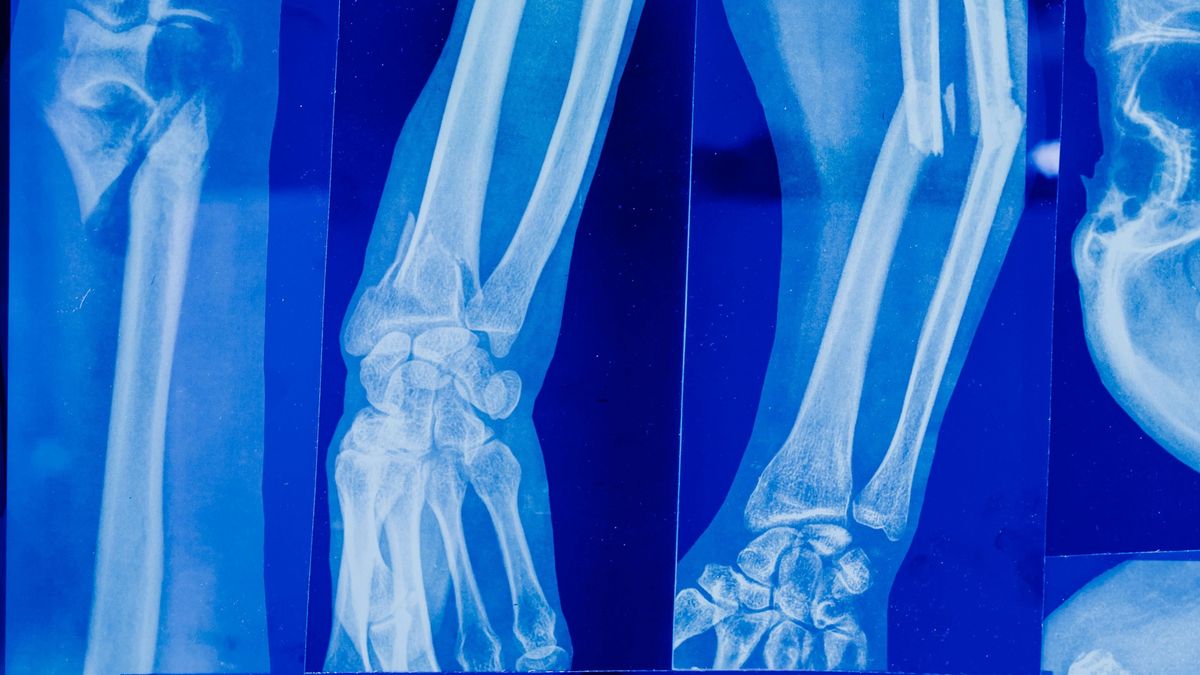

Milliók élnek együtt a néma gyilkossal, ami akkor csap le, amikor a legkevésbé számítunk rá. A csontritkulás miatt egy rossz mozdulat vagy egy apró botlás is végzetes lehet, de van megoldás, ami a konyhádban kezdődik.

Ahogy telnek az évek, mindannyian bizonytalanabbá válunk a lábunkon. Ami fiatalon csak egy apró botlás, az idősebb korban már tragédiához vezethet: a csontritkulás miatt egy egyszerű esés is súlyos töréssel végződhet. A statisztikák ijesztőek: évente több százezer „törékenységi” baleset történik, az 50 feletti nők több mint fele pedig legalább egyszer elszenved valamilyen csonttörést élete során.

A betegség nem véletlenül kapta az üvegcsontúság nevet, hiszen a csontok szerkezete belülről válik lyukacsossá és sérülékennyé. Ella Kaur táplálkozási szakértő szerint azonban nem kell beletörődnünk a sorsunkba.

A nők számára különösen a menopauza környékén válik élessé a helyzet, mivel az ösztrogénszint csökkenésével a leépülés felgyorsulhat, akár évi 3%-ot is veszíthetnek a csontsűrűségükből. De van remény: a csont élő szövet, ami folyamatosan épül és lebomlik, így a megfelelő tápanyagokkal visszavághatunk a folyamatnak.